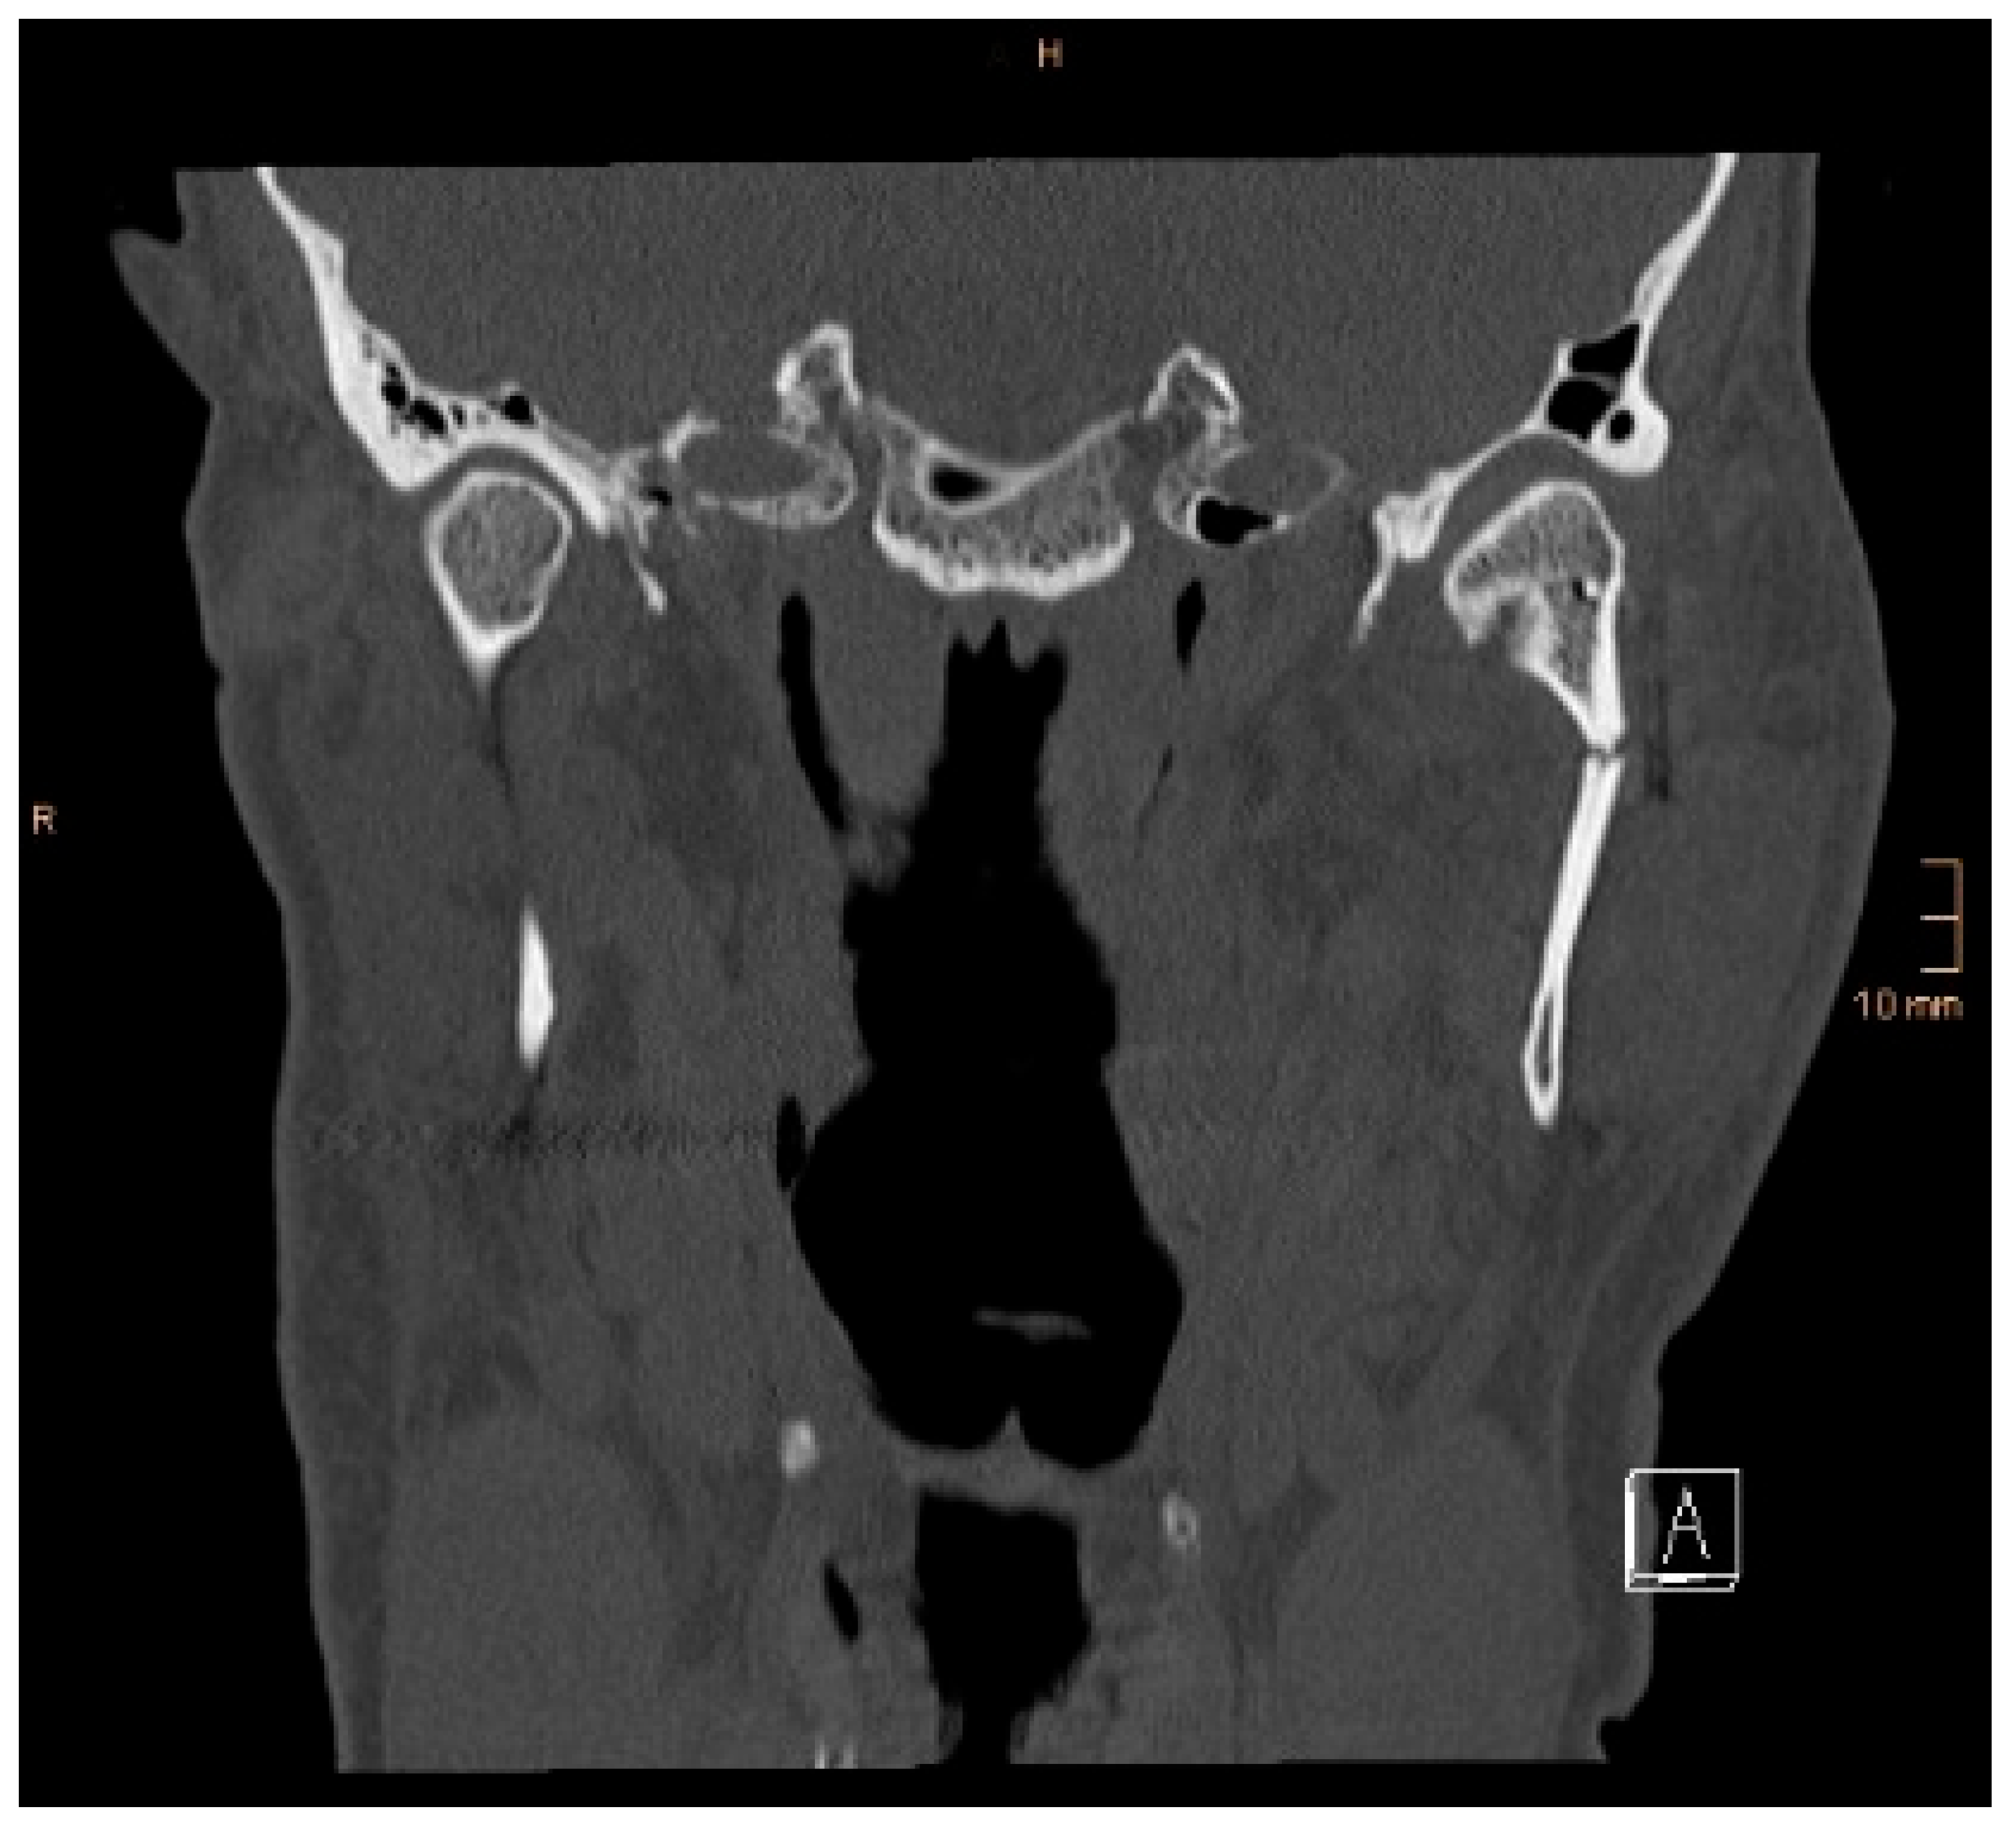

Figure 5. Coronal CT scan showing both condyles after ORIF. A widening of the mandible, caused by a small lingual gap that persisted even after lag screw osteosynthesis at the symphysis, resulted in an angulation of the condylar neck on the right-hand side (same patient as in Figure 3 and Figure 4). The image shown was taken on the third postoperative day after drainage removal and the situation did not worsen over time (last follow-up 1 year postop).